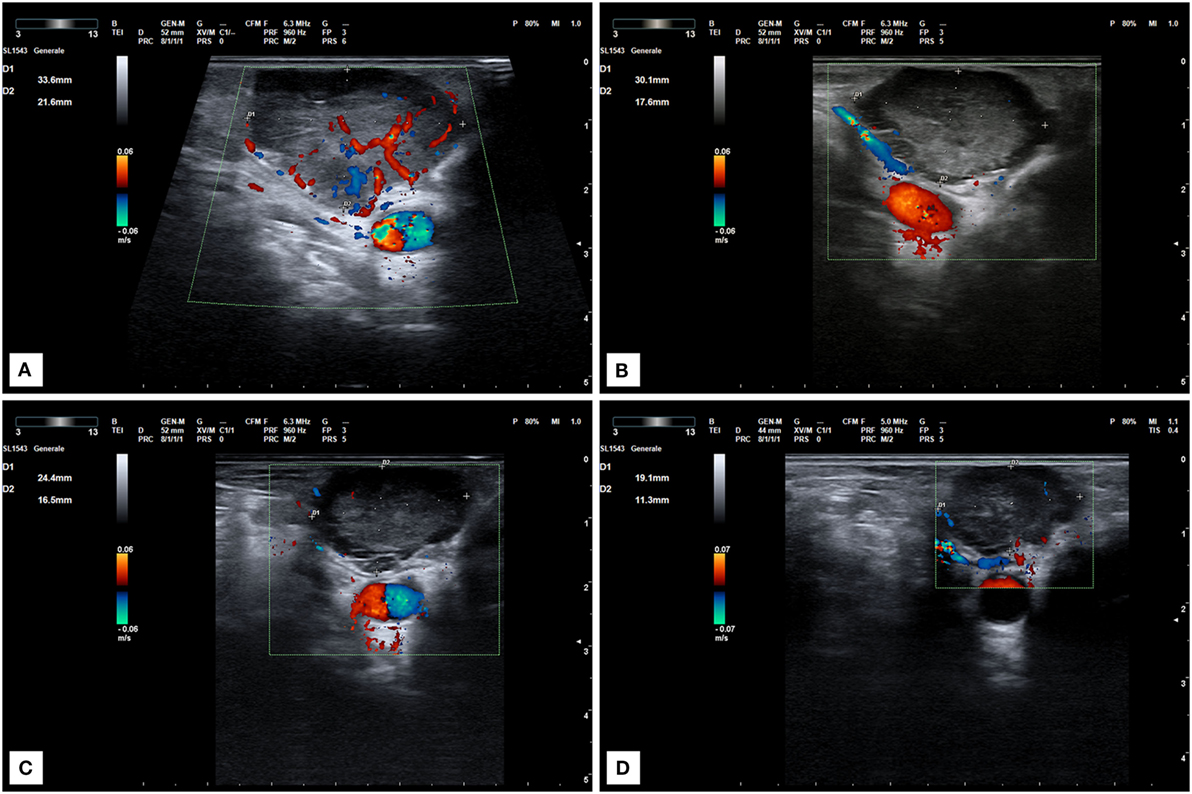

At our first observation in May 2017, basal Tg was 500 ng/ml, Tg-Ab <20 U/ml, TSH 0.015 mU/l, and daily levothyroxine intake was 137.5 mcg. Diplopia and right palpebral ptosis had started about 1-month earlier. A subsequent 18FDG PET/CT scan showed intense glucose metabolism in the basisphenoid region (Figure 1) and a gadolinium-enhanced brain MRI scan revealed a mass in the right cavernous sinus measuring 2.5 cm × 2.0 cm × 1.8 cm, with a low signal in T2 and enhancement on post-contrast images, which was compatible with a metastasis. The lesion encapsulated a 2-cm segment of the right internal carotid artery, without causing luminal narrowing (Figures 2A–C). Given the patient’s non response to RAI treatment and the locally advanced and progressively increasing metastatic burden, lenvatinib was initiated in June 2017. Because the intracranial lesion encapsulated a considerable portion of the right internal carotid artery, we started with a low dose (10 mg daily) to avoid the risk of artery damage consequent to rapid tumor shrinkage. An MRI performed about 30 days later showed that the metastasis in the right cavernous sinus was significantly smaller and that the integrity of the internal carotid was preserved (Figures 2D–F). Diplopia and palpebral ptosis progressively regressed with treatment and the patient did not complain of any cerebral symptom. Basal Tg declined to 338.4 ng/ml without Tg-Ab, in line with a reduction in neck lesions volume (Figure 3).

Figure 3. Ultrasound scan of a locally recurrent neck lesion in right supraclavicular region. (A) Imaging before lenvatinib start. (B) Ultrasound scan after 1 month of therapy at 10 mg daily. Tumor vascularization is significantly reduced. (C,D) Progressive tumor reduction after 2 (C) and 6 months (D) of treatment at the same dose.